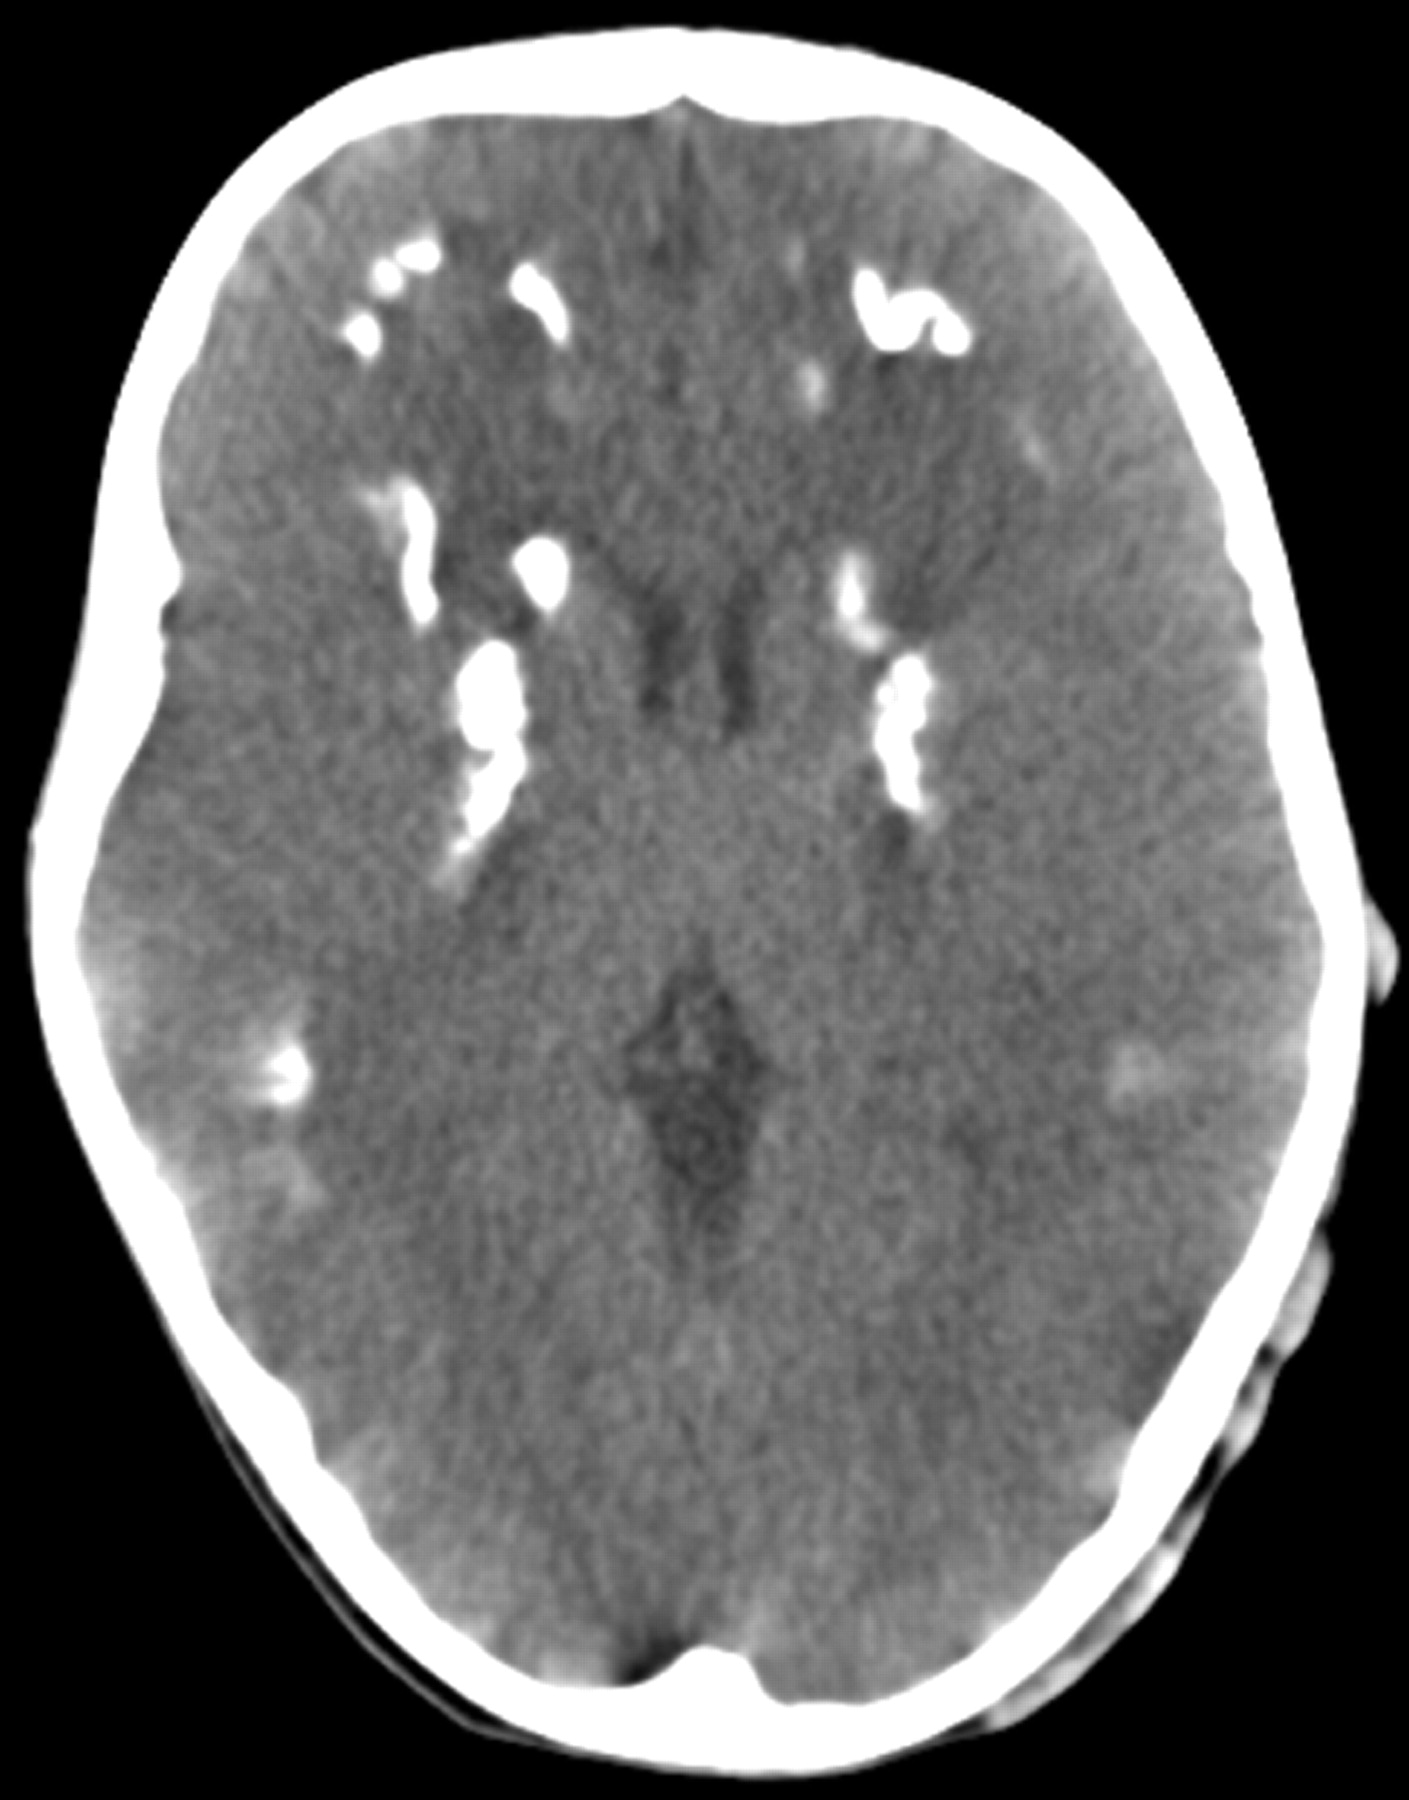

A CT scan suggested that the mass was a plexus of dilated scalp veins filled through the prominent mastoid emissary foramen (Fig 1). There were also diffuse calcifications on the bilateral basal ganglia and subcortical white matter in CT scan (Fig 2). Carotid artery angiography revealed grossly anomalous intracranial venous drainage (Fig 3). There was remarkable stenosis of the left transverse sinus and atresia of both sigmoid sinuses with florid collateral scalp vein drainage via the prominent mastoid emissary vein. Additionally, after manual compression of the mastoid emissary foramen, there was no other obvious collateral drainage passageway. On the basis of these findings, together with the normal growth and life of the patient, he was discharged with close follow-up.

Noncontrast axial CT scan shows diffuse calcification on the bilateral basal ganglia and subcortical white matter.